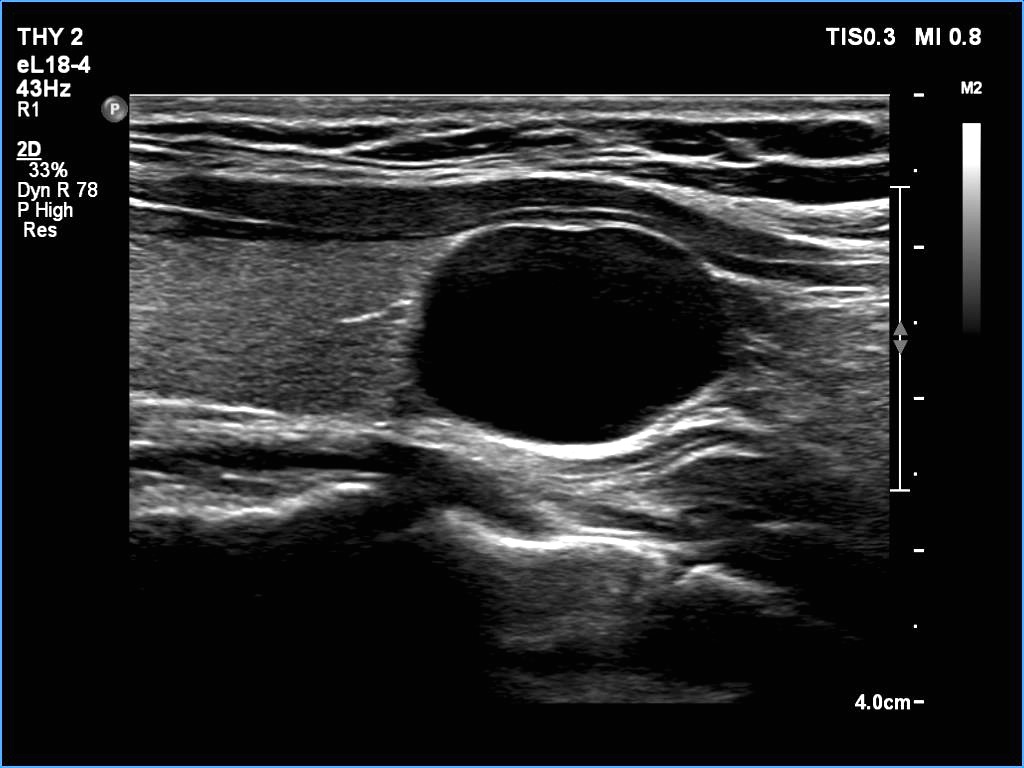

Transverse scan |

Longitudinal scan |

This is an almost completely cystic lesion, however it does not meet the criteria of a pure cyst. The wall thickening (yellow arrows) is ambiguous but there is a tiny solid-appearing area in the dorsal wall (red arrows). In systems which do not use the term 'almost completely cystic lesion', this nodule should be categorized as a peripheral-type cyst.